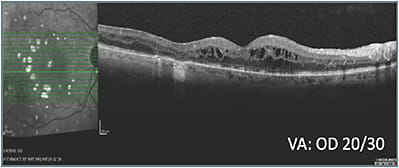

When this 69-year-old male with a history of PDR, DME, and multiple treatments, including laser, was referred from another practice, it was noted that he had poor response to prior treatment. The patient was pseudophakic and did not have glaucoma. His visual acuity was 20/50 OD and 20/30 OS. OCT indicated the need for treatment (A).